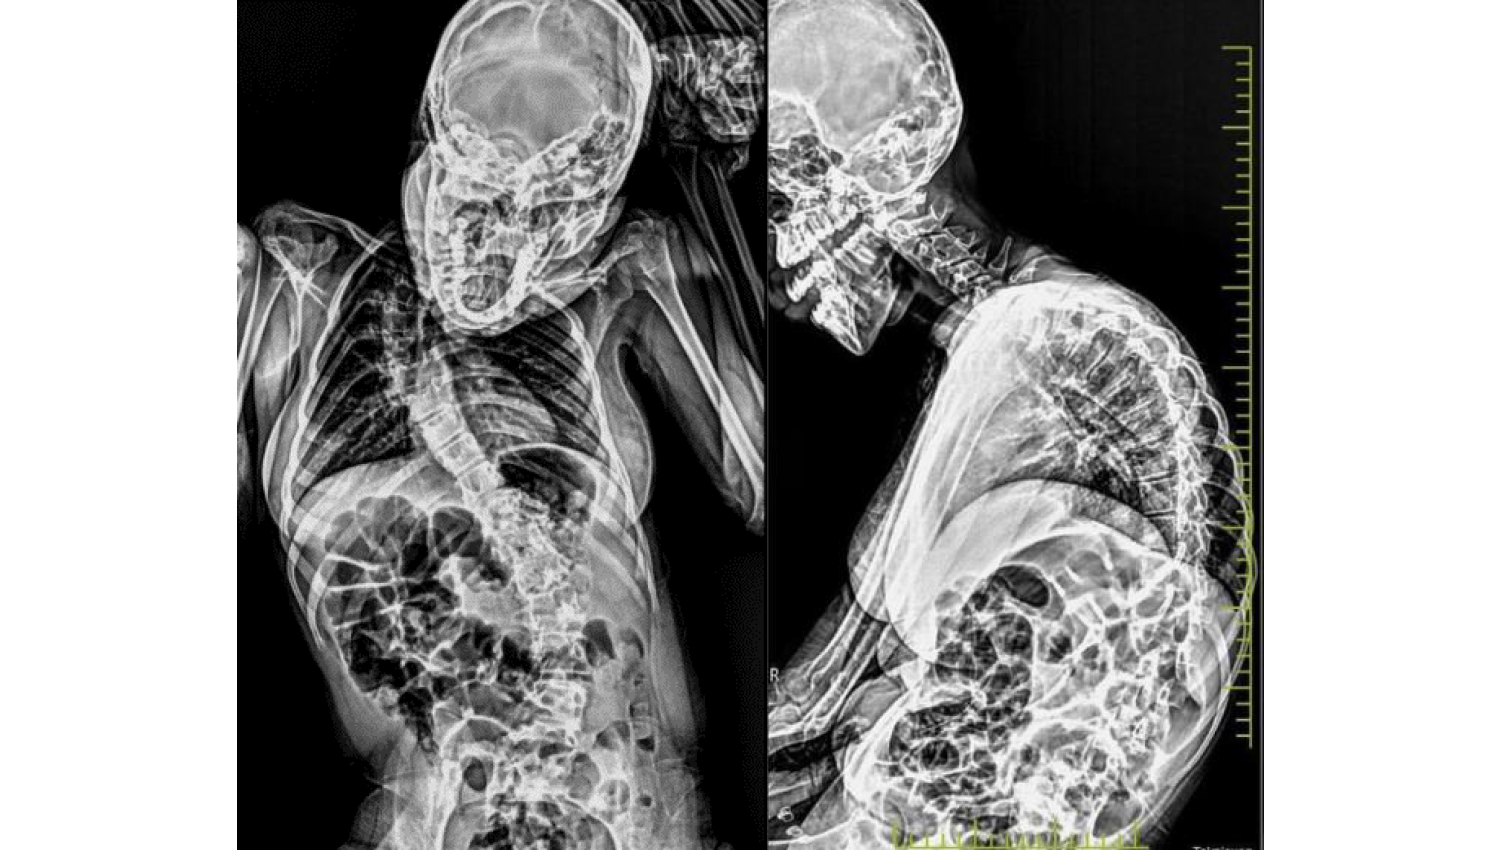

4.Before and after radiological view.